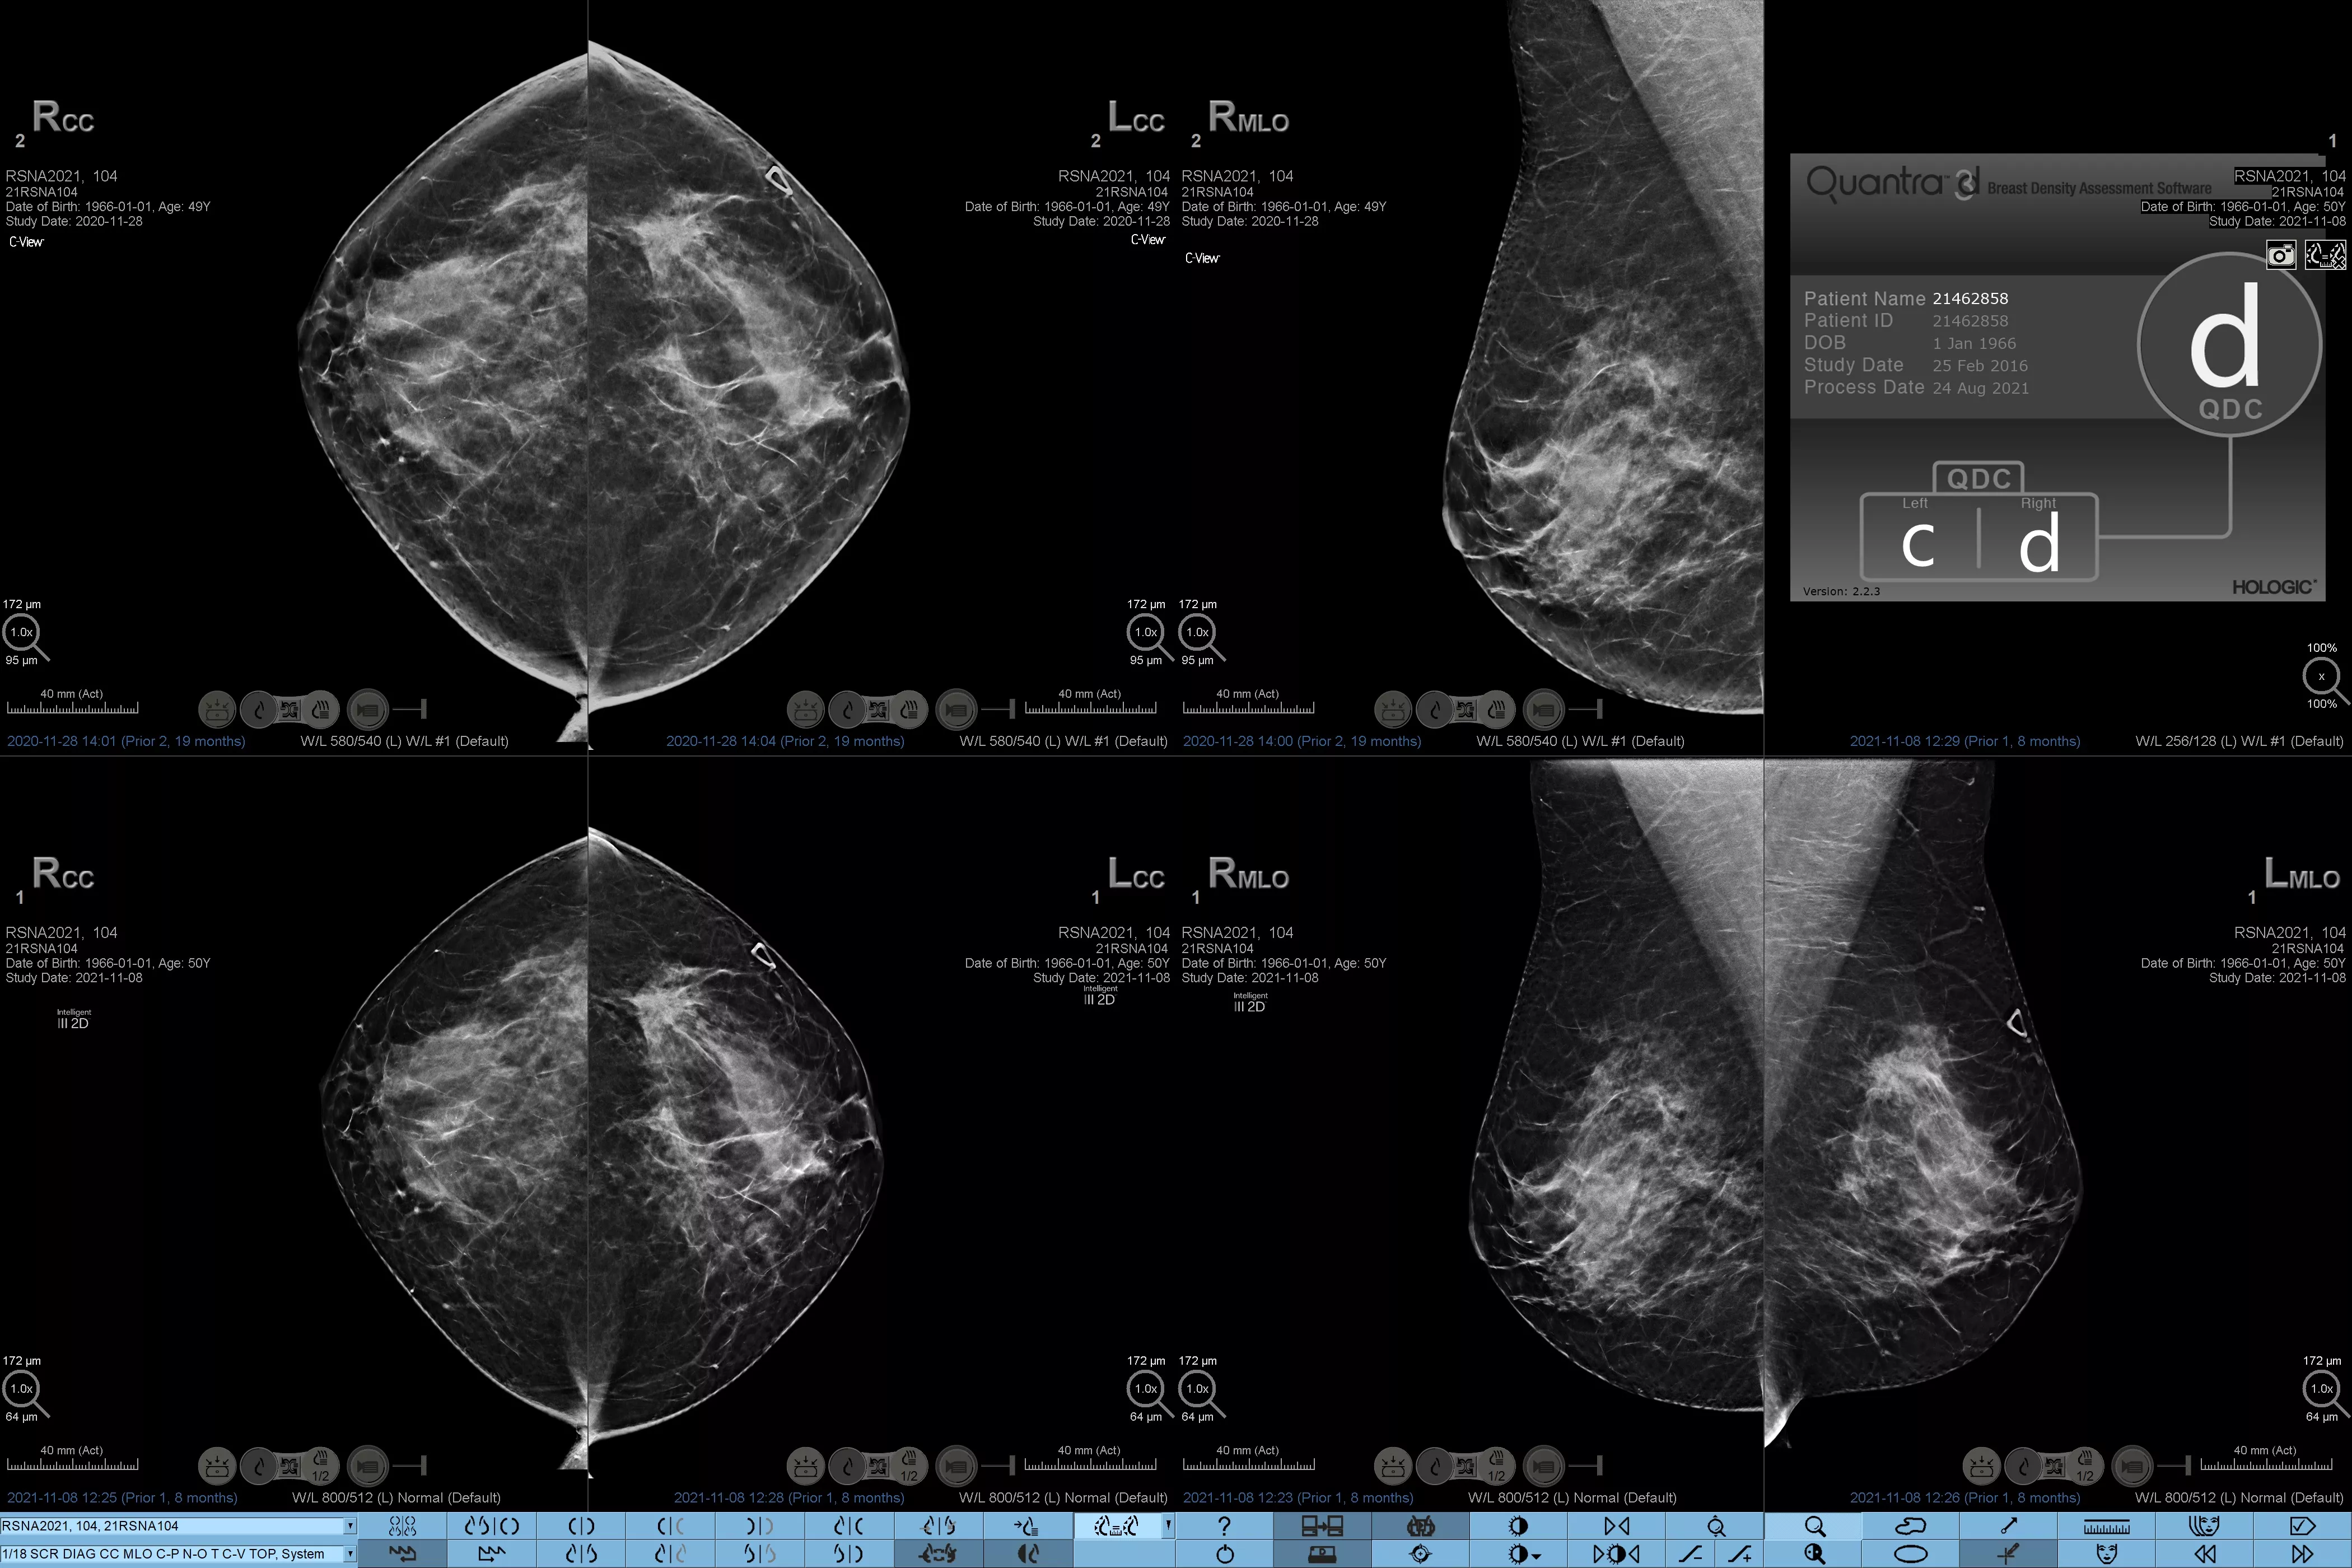

Det är känt att en hög brösttäthet ökar en kvinnas risk för bröstcancer.1 Behovet av noggrann och opartisk analys är därför kritiskt. Med hjälp av maskininlärning analyserar Quantra Technology-programvaran både 2D™- och tomosyntesbilder för fördelning och textur av parenkymal vävnad. Den kategoriserar bröst i fyra bröstkategorier utifrån sammansättning enligt riktlinje från American College of Radiology (ACR) BI-RADS Atlas 5th Edition.2

Objektiv maskininlärningsalgoritm som tilldelar en kategori för brösttäthet baserat på analys av bröstvävnadens textur och mönster.

Den opartiska algoritmen i programvaran analyserar både 2D- och tomosyntesbilder för att:

• Övervinna subjektivitet vid visuell bedömning, vilket ger mer konsekvent och tillförlitlig bedömning*

Riskkategorier8